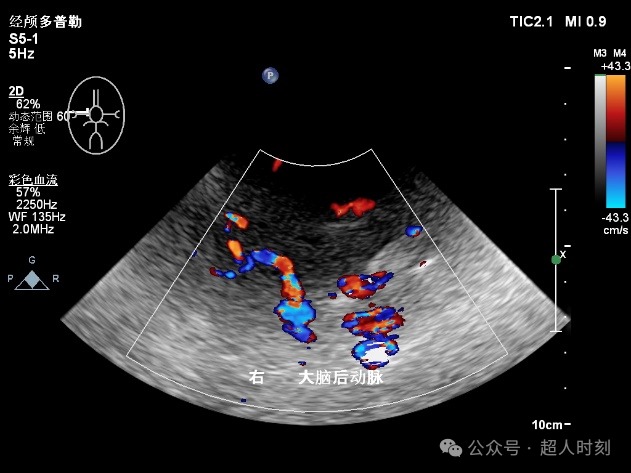

图5c 右大脑后动脉狭窄

图5d 右大脑后动脉血流增快频谱(VP:140cm/s)